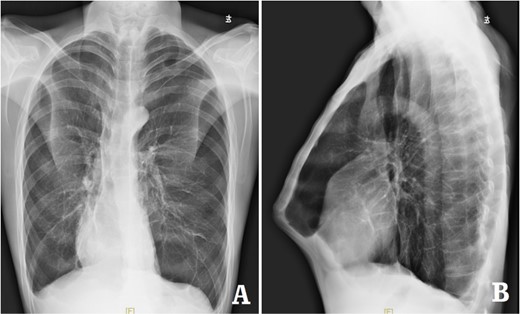

The patient was a 29-year-old male. He was found to have protrusive deformity on the anterior chest wall since childhood. The deformity was not serious in early years, but worsened after adolescence, with the lower part of the sternum protruding at an acute angle. At the age of 25, he developed right spontaneous pneumothorax and received surgical treatment at local hospital, but his thoracic deformity was not treated. As the deformity continued to worsen, which seriously affected the appearance of the chest wall, the patient was admitted to our hospital for surgery. Preoperative physical examination showed that the anterior chest wall was protrusive seriously, with a sharp tip protruding forward. The rib arches on both sides were slightly depressed (Fig. 1). Imaging examination showed that the anterior chest wall was protrusive, and the lower end of the sternum was at the forefront of the protrusion. His heart moved to the right, and the rib arches were slightly depressed (Figs 2–4). The operation was performed under general anesthesia. Two longitudinal incisions were made on both sides of the chest wall respectively. The incisions were located between the front axillary line and the median axillary line, with the length of ~5 cm. The chest wall muscles were dissected to expose the ribs in the incisions. Two tunnels were made on the highest plane of the protrusion, with interval of 3 cm. The tunnels were located in the deep layer of the chest wall muscles and bone structures. Two steel bars were inserted into the tunnels to flatten the front protrusion with their median parts, and then, both ends of the steel bars were fixed on the ribs at the lateral chest wall. The above operation was the main content of Wenlin procedure [1, 2, 5]. After this procedure was completed, the lower part of the chest wall showed obvious depression, especially in the middle of the rib arches. Then, Wung procedure was performed [6]. A third tunnel was made at the plane passing the midpoint of the rib arch, which passes through the bilateral thoracic cavity. The third steel bar was inserted into the tunnel. After the steel bar was rotated and fixed to the ribs, the depression was supported totally. The incisions were closed, and the operation was completed. The deformity of anterior chest wall disappeared completely after the operation (Fig. 5). The operation time was 75 min. The intraoperative bleeding volume was 40 ml. Postoperative X-ray examination showed that the bars position was normal (Fig. 6). He was discharged 7 days after operation. Follow up for 1 year showed satisfactory recovery. The steel bars were taken out 1 year after the operation, and the appearance of the thorax was normal and there was no recurrence (Fig. 7).

X-ray examination after operation. (A) Posteroanterior radiograph; and (B) lateral radiograph.